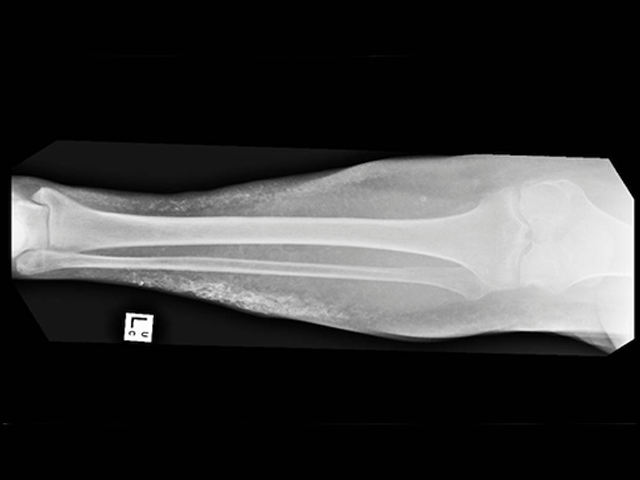

Acquired plate-like osteoma cutis

X-rays should be undertaken during childhood to identify skeletal problems, as these can be masked by obesity.